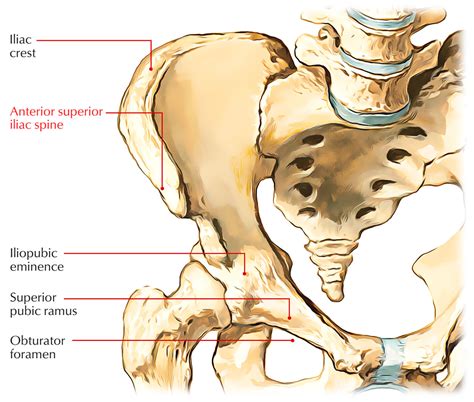

Iliac crest apophysitis occurs when the growth plate at the iliac crest becomes inflamed due to repetitive stress and overuse. The iliac crest is a common site for muscle attachments, including the abdominal muscles and the gluteal muscles. During periods of rapid growth, the growth plates (apophyses) are particularly vulnerable to injury. This condition is more prevalent in adolescents who are actively involved in sports that require repetitive hip movements, such as soccer, basketball, and track and field.

Diagnosing iliac crest apophysitis typically involves a combination of a physical examination and medical history. A healthcare provider will assess the symptoms and perform a physical exam to identify tenderness and swelling at the iliac crest. Imaging tests, such as X-rays or MRI scans, may be ordered to rule out other potential causes of pain and to confirm the diagnosis.